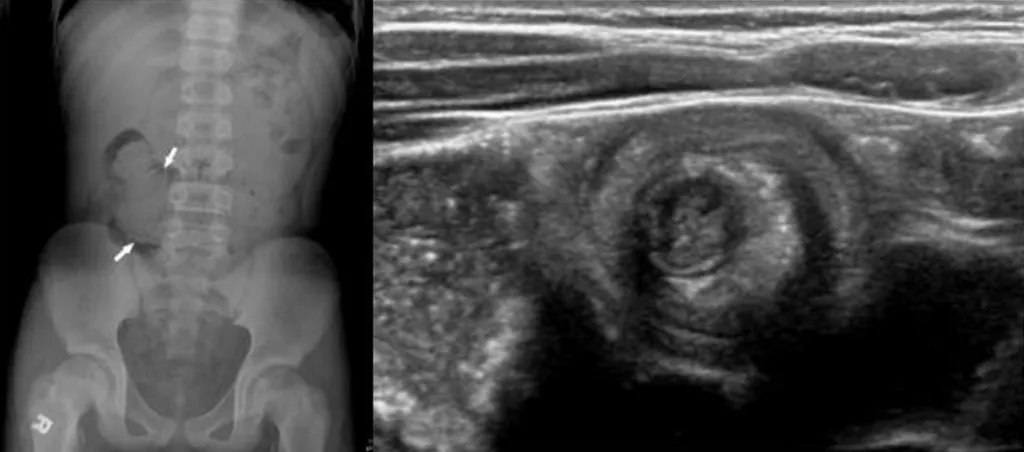

【114-2 醫學(三) 第75題】

12 歲的張小弟,近三日無正常解便,早上媽媽發現他解出黏液狀的排泄物,被家人送到急診室。醫師診察後安排腹部X光及腹部超音波檢查,如圖所示。張小弟最有可能罹患下列何者疾病?

詳解

破題關鍵

這題的解題核心在於辨識腹部超音波影像中典型的「靶心徵」(target sign),這是腸套疊最明確的診斷依據,再結合病童的臨床症狀,就能快速鎖定答案。

選項拆解